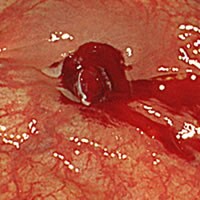

当日ポリープ除去手術が可能です

診断から治療まで一貫して対応ができるため、検査の際に万が一、ポリープを発見した際には即日の切除手術を行うことも可能です。

大腸ポリープ切除

内視鏡での観察中に大腸ポリープが見つかることがありますが、ポリープを速やかに切除することに

なった場合、少し検査時間が延長されますのでご了承ください。

(ポリープ1個の切除に、5~10分の時間を要します)検査終了後